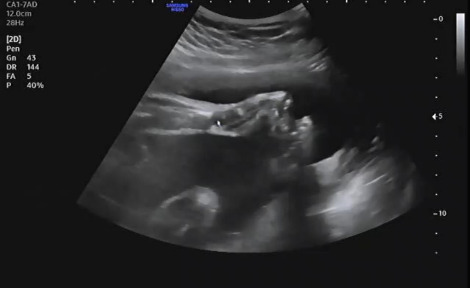

햇님이의 상태를 확인하고 아이의 자세 및 위치를 알려줬다. 다행히 머리가 아래로 향하게 있어 이대로 막달까지만 잘 있어준다면 자연분만이 가능할 것 같다고 이야기했다. 앞으로 짧다면 짧지만 길다면 긴 약 10주간의 시간이 남았는데 그동안 아기가 건강하게 세상으로 나와 만날 준비를 해 주길 희망했다.